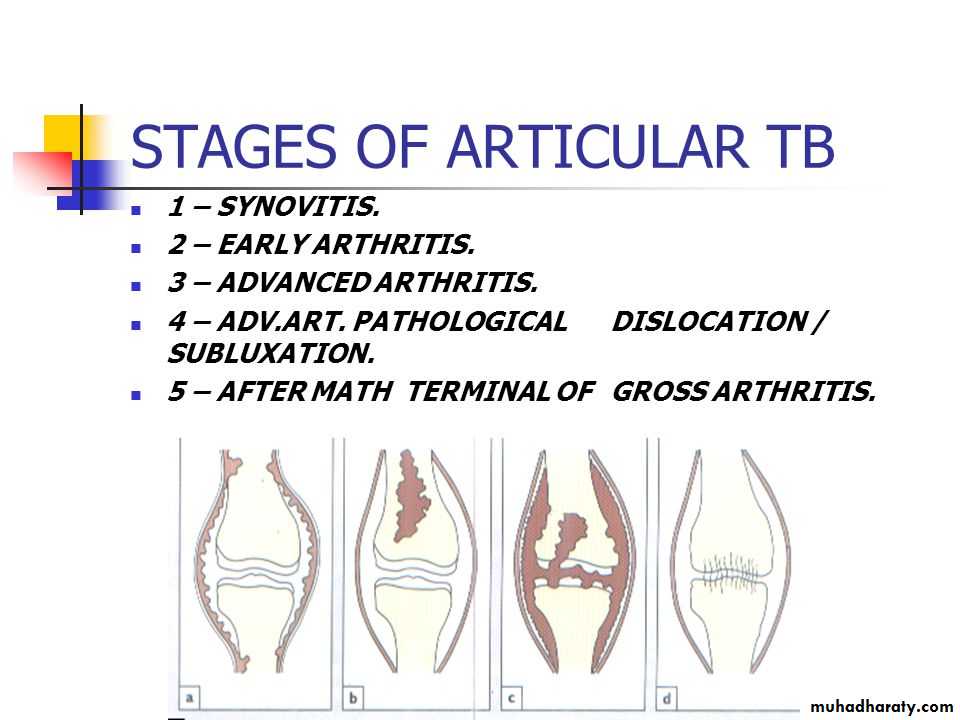

The disease may begin as synovitis (a) or osteomyelitis (b).From either, it can extend to become a true arthritis (c); not all the cartilage is destroyed, and healing is usually by fibrous ankylosis(d).

If the synovium is involved, it becomes thick and oedematous, giving rise to a marked effusion.

If unchecked, infection extend into the surrounding soft tissues to produce an abscess with minimal inflammatory reaction‘cold’ abscess.